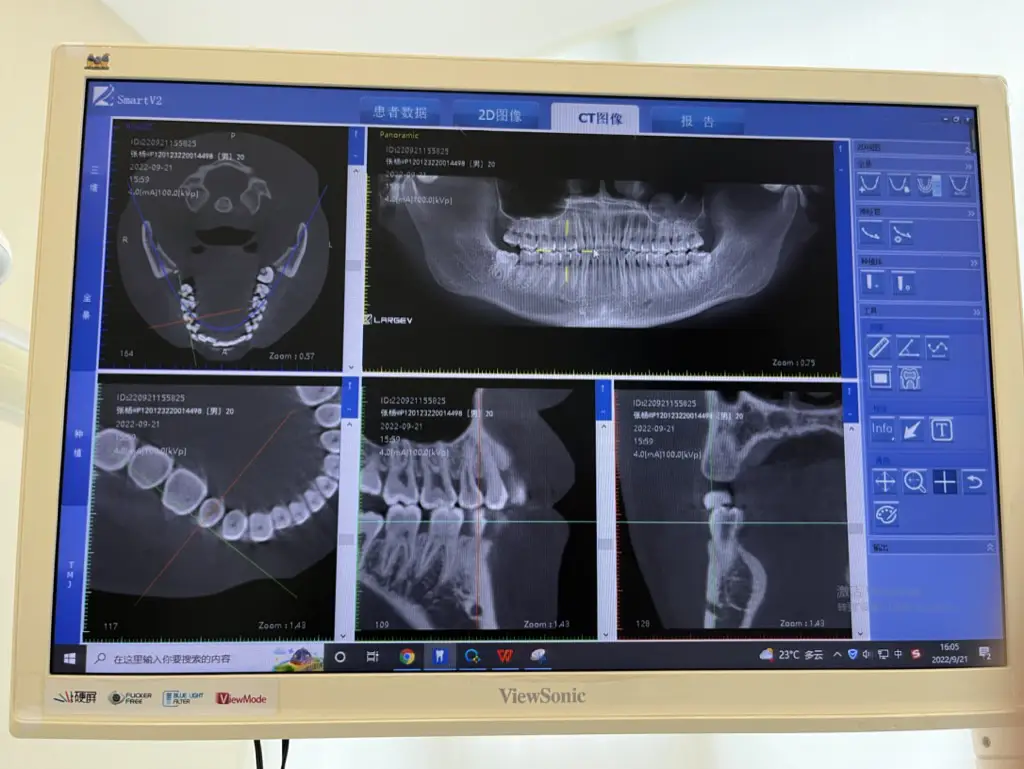

开了一些治疗牙龈发炎的替硝唑片,拍了一个更昂贵的牙CT:

医保尚未到达起付线,微信支付了200多现大洋。